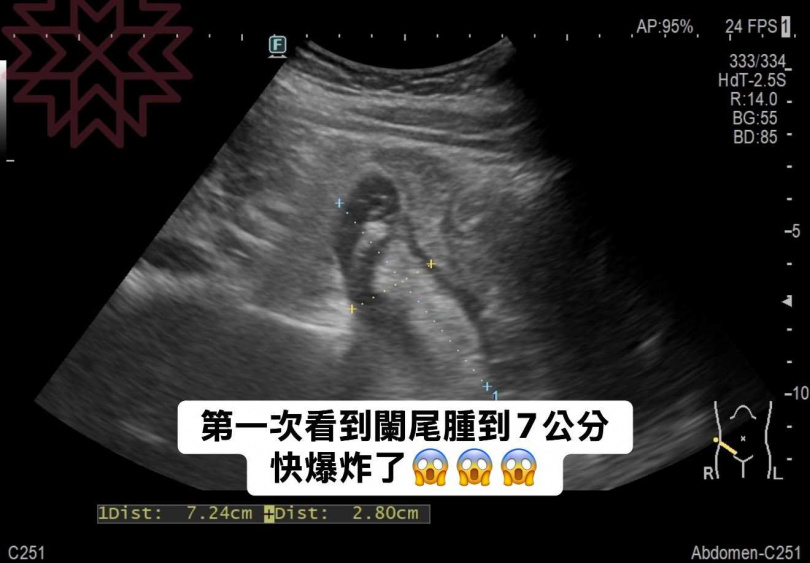

為進一步確認,林相宏醫師立即為她安排腹部超音波檢查,結果證實,女病患的的闌尾腫脹達7公分,屬於罕見嚴重的闌尾炎情形,隨即安排病患進行手術。手術過程中,又發現女病患的闌尾已嚴重發炎,幾乎腫到爆裂,所幸並未發展成腹膜炎。